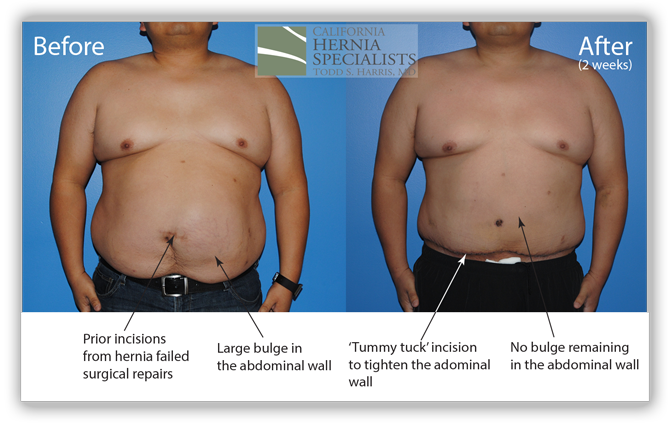

A ‘tummy tuck’ incision was used to help tighten and remove excess skin and the old scar. The old mesh had completely separated from the muscle and was stuck to the small intestines internally. Careful removal of the mesh was required to free the intestine from the hernia. The muscle was closed and a new piece of advanced mesh was placed under the muscle to reinforce the repair. The images below are from before and after his hernia surgery.

In the images below we compare the pre-operative photos to the post-operative photos taken just 2 weeks after his surgery.

The patient continued to lose weight after his surgery. He was followed for 6 months and did very well throughout this time returning to normal activities after about 4-6 weeks.